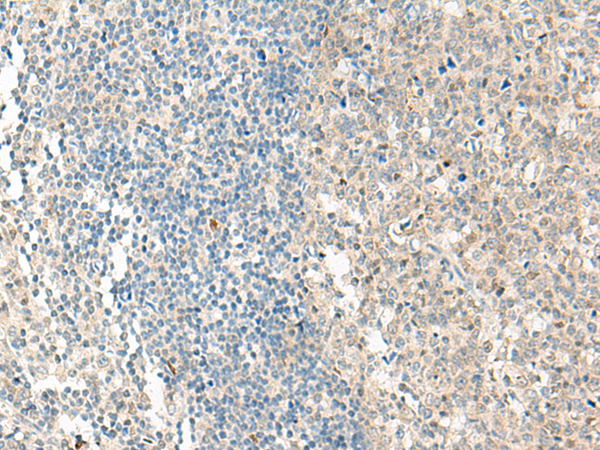

分类: 科研抗体货号: P13514别名: MRGD; TGR7应用: IHC反应种属: Human